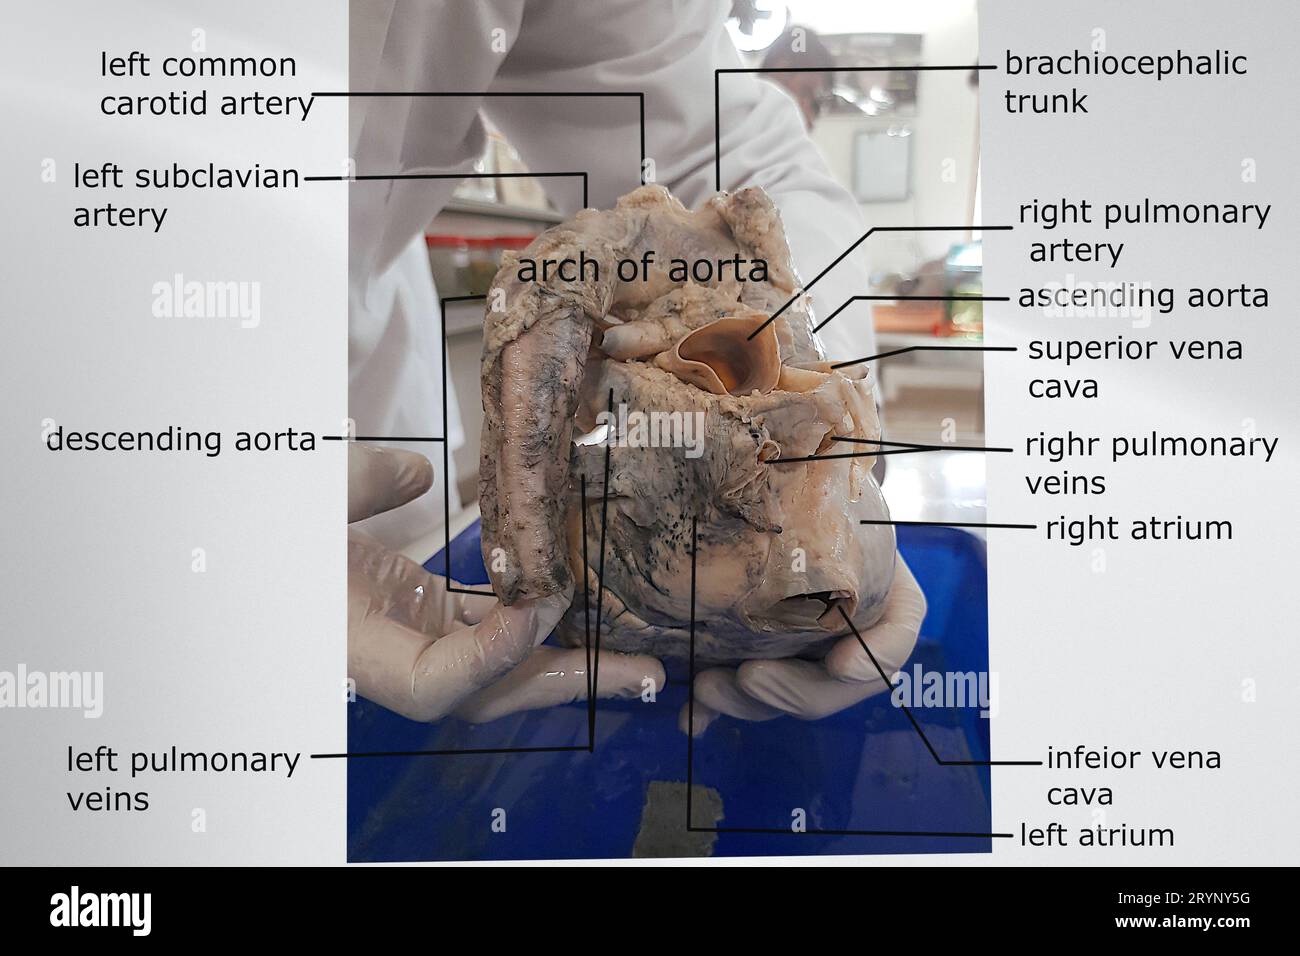

anatomy of the posterior view of heart with attached great vessels Stock Photohttps://www.alamy.com/image-license-details/?v=1https://www.alamy.com/anatomy-of-the-posterior-view-of-heart-with-attached-great-vessels-image567809804.html

anatomy of the posterior view of heart with attached great vessels Stock Photohttps://www.alamy.com/image-license-details/?v=1https://www.alamy.com/anatomy-of-the-posterior-view-of-heart-with-attached-great-vessels-image567809804.htmlRF2RYNY5G–anatomy of the posterior view of heart with attached great vessels